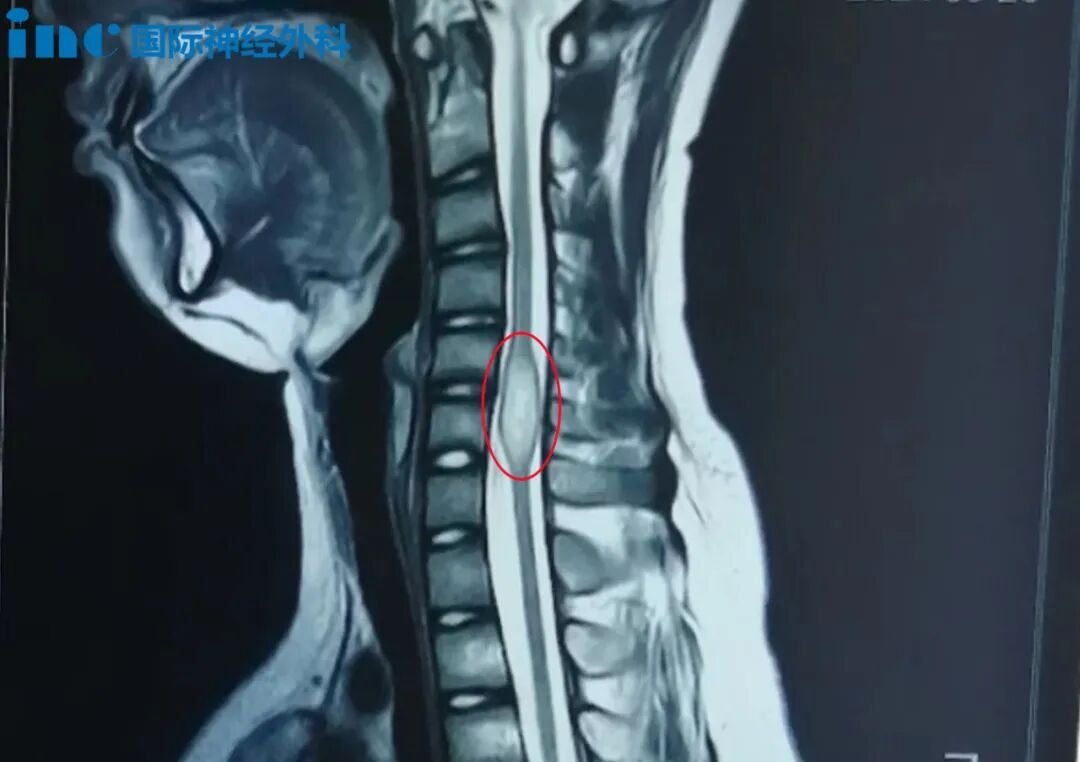

"早发现、早治疗"是医学界长期以来的共识,然而面对复杂的神经外科疾病,患者往往陷入茫然:同样是脊髓肿瘤,有的医生说要尽快手术,另一个医生却说暂时不建议动刀,究竟该听谁的?...